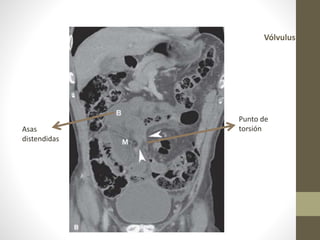

Vólvulos

• Torsión de asa intestinal > 180 grados en su propio eje.

• Designado para ciego, colon transverso, flexión esplénica y

el colon sigmoide (65%).

• Descompresión por endoscopia o por proctorectosigmoidoscopio

rígido o flexible (85 – 95%)

• Indicación quirúrgica:

• Hallazgos peritoneales, sepsis, shock.

• Tiempo de evolución.

• Cecostomia o cecopexia.

• No es recomendada-.

Vólvulus

Asas

distendidas

Punto de

torsión

Vólvulos • Torsión deasa intestinal > 180 grados en su propio eje. • Designado para ciego, colon transverso, flexión esplénica y el colon sigmoide (65%).

• Descompresión porendoscopia o por proctorectosigmoidoscopio rígido o flexible (85 – 95%) • Indicación quirúrgica: • Hallazgos peritoneales, sepsis, shock. • Tiempo de evolución. • Cecostomia o cecopexia. • No es recomendada-.